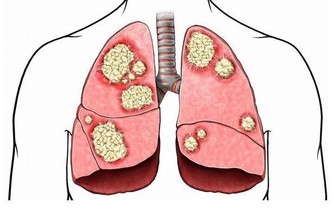

6、乳腺炎

乳腺炎一般發生在產後哺乳期女性身上,乳房有自覺疼痛感,乳房表面皮膚紅熱,用手觸摸有硬塊。期間多注意休息,不能做重體力勞動,保持積極樂觀情緒,若有異常需及時治療。